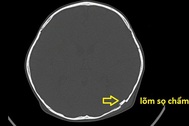

ThS.BS Lê Thị Nga - Khoa Phẫu thuật tạo hình thẩm mỹ và hàm mặt cho biết, bé trai 10 tuổi ở Hà Nội nhập viện trong tình trạng mặt sưng nề, bầm tím nhiều vùng mũi, biến dạng lõm vùng mũi phải. Kết quả chụp CT hàm mặt, xác định có tổn thương gãy xương chính mũi phải.

Cú văng mạnh của "đồ long đao" khiến cậu bé gãy xương mũi (Ảnh: Bệnh viện cung cấp).